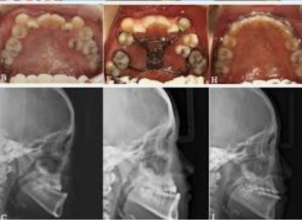

Maxillary prognathism is a dental and facial condition in which the upper jaw extends forward more than normal in relation to the lower jaw. This condition can affect the overall balance of the face and may lead to difficulties with proper bite alignment, chewing, and speech. In many cases, maxillary prognathism develops due to genetic factors, abnormal jaw growth, or developmental conditions that affect the structure of the facial bones.

- Gummy smile (Vertical maxillary excess).

- Anterior-posterior discrepancies of the maxilla.

- Constricted arch.

- Pre-surgical Orthodontics: Often needed before the actual surgery takes place. Imaging: X-rays and CT scans are required.